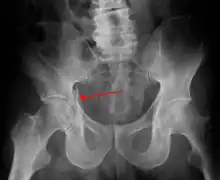

Radiologie standard

De nombreuses incidences radiologiques ont été évaluées par le passé. Une incidence de face du bassin est la première radiographie à réaliser dès l’admission d’un patient pour lequel on suspecte une lésion de l’anneau pelvien. Les radiographies standards révèlent 90 % des fractures du bassin[3].

Différentes incidences obliques sont indiquées en cas de suspicion de fracture du bassin non objectivable sur la radiographie de face. En en cas de suspicion de lésions particulières (fracture isolée du sacrum, fracture du cotyle…) des radiographies spécifiques peuvent être demandées.

Scanographie

Le CT-scan a pris une place considérable dans l’imagerie des traumatismes du bassin. Il est devenu possible d’obtenir des reconstructions en 3D permettant une meilleure visualisation anatomique avec évaluation des saignements dans le péritoine ou le rétropéritoine. Il permet aussi de confirmer une dislocation de hanche avec fracture du cotyle[10],[11].